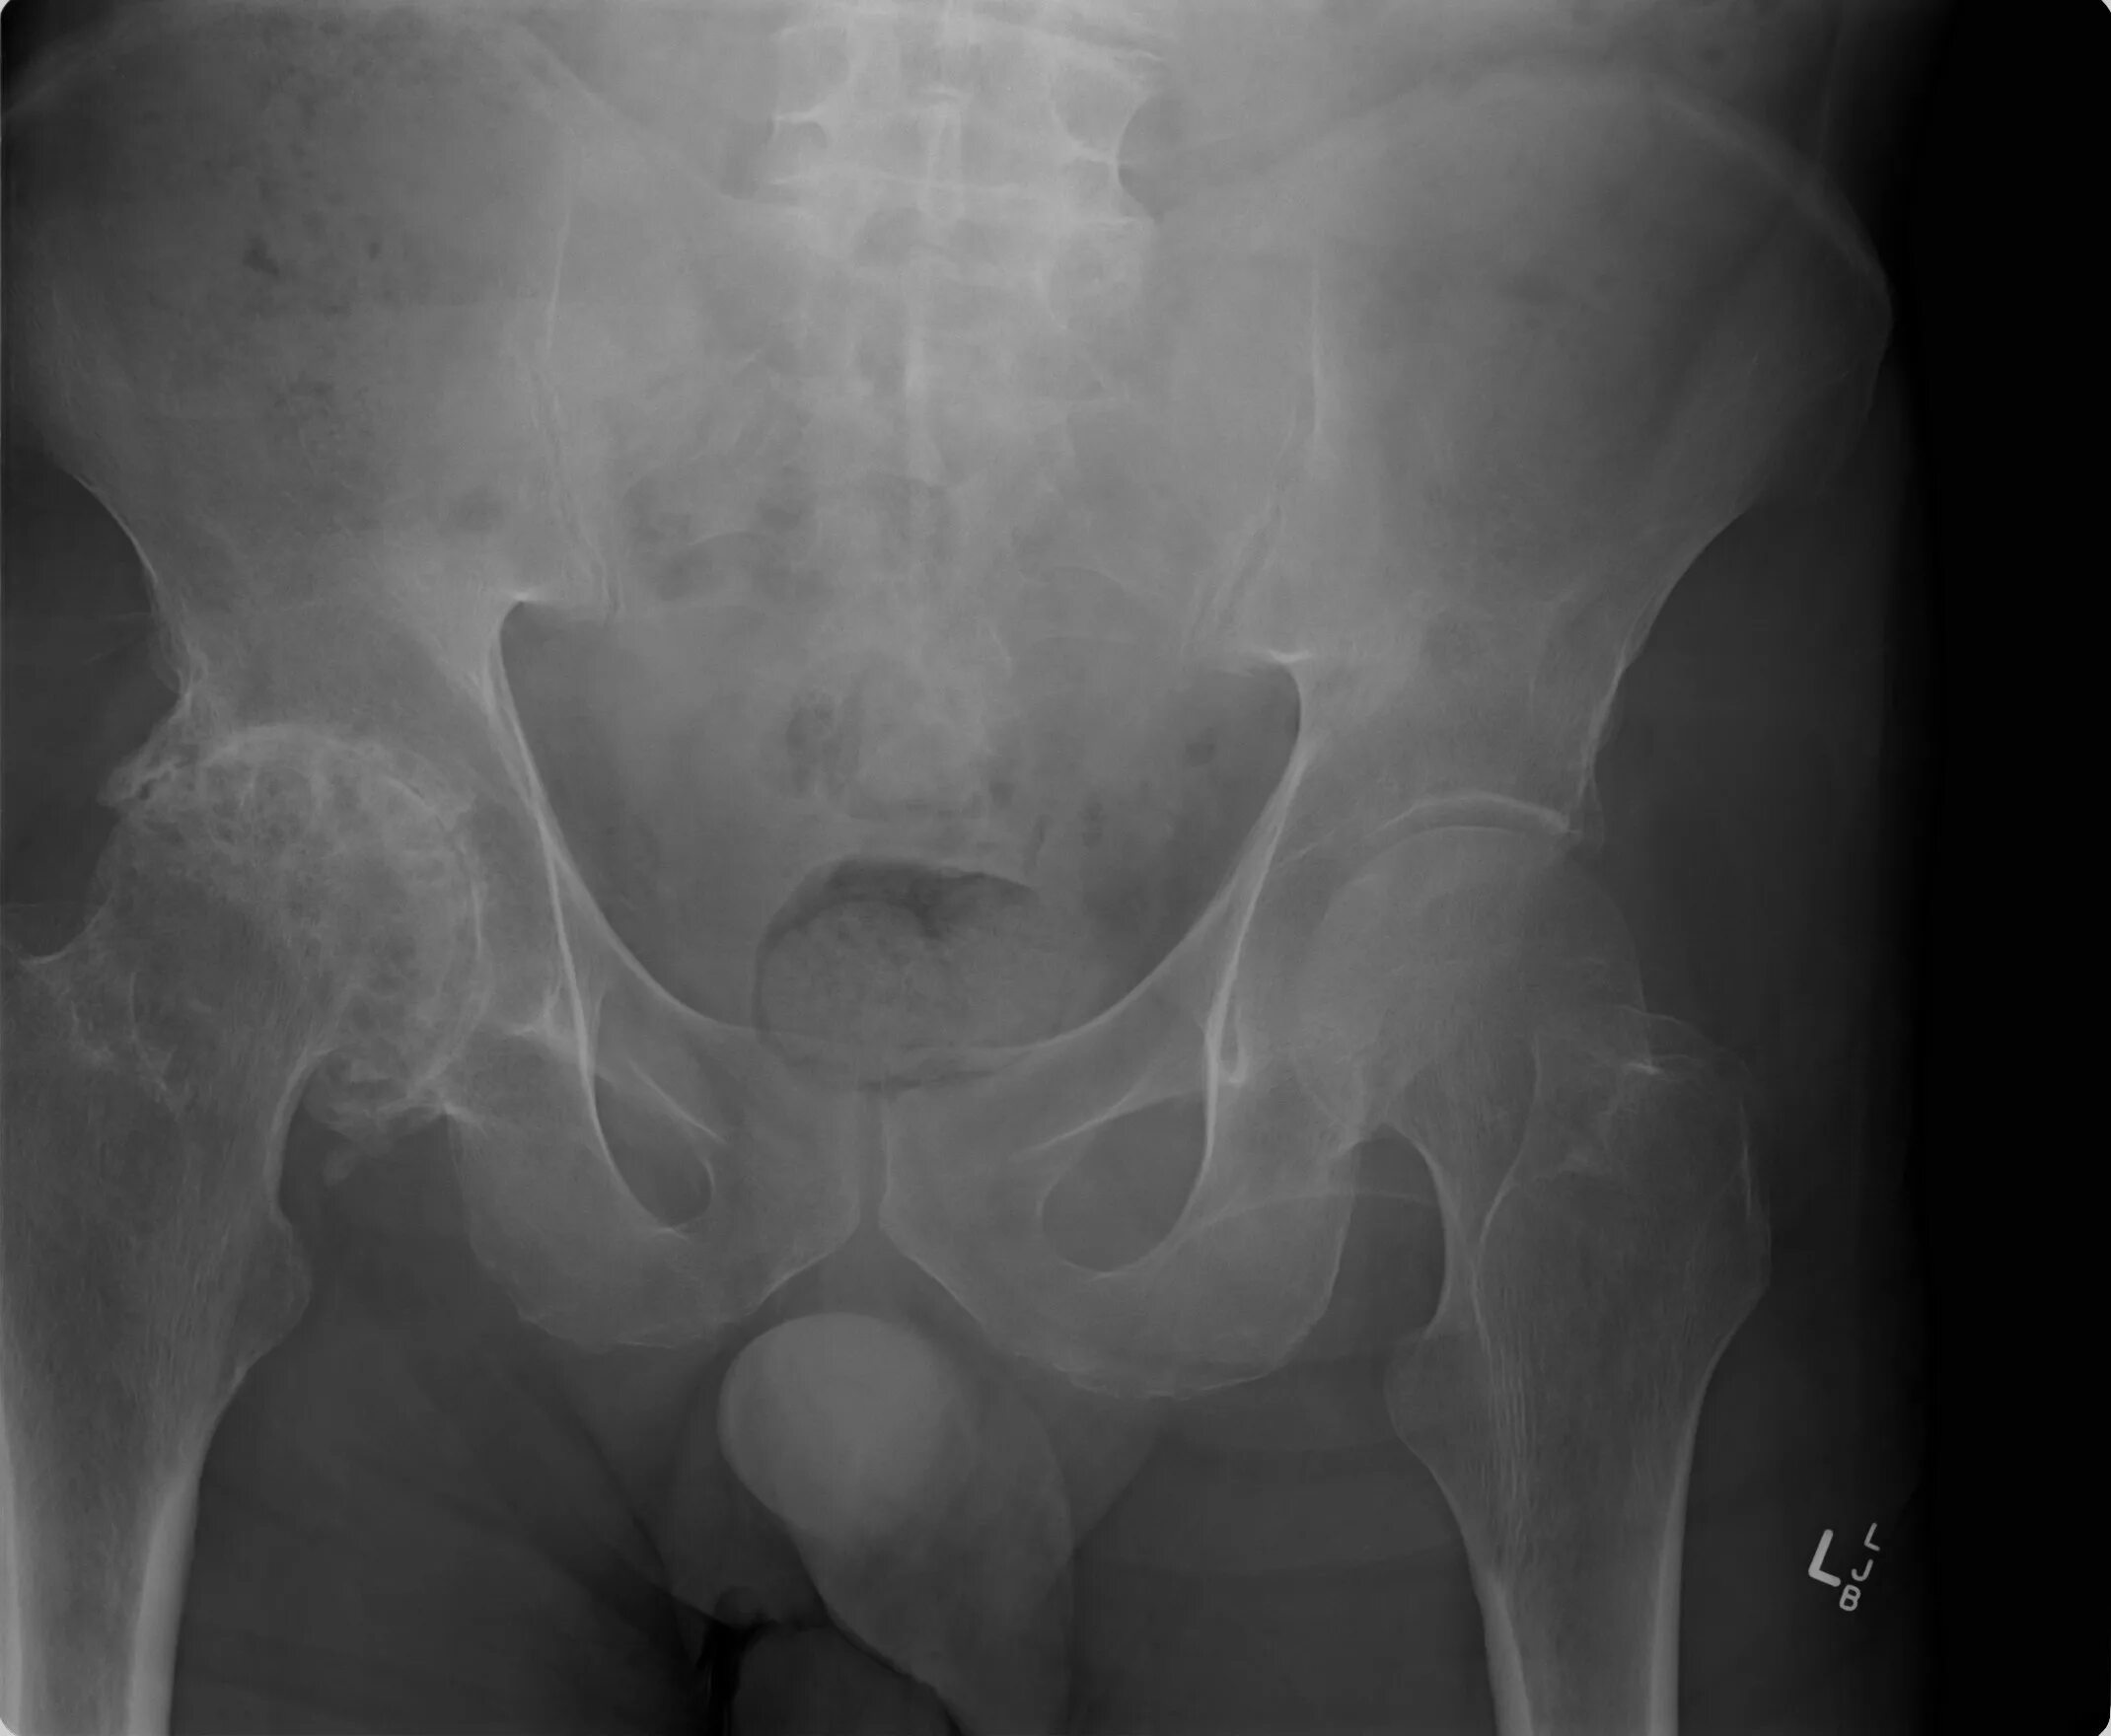

Обследование тазобедренного сустава